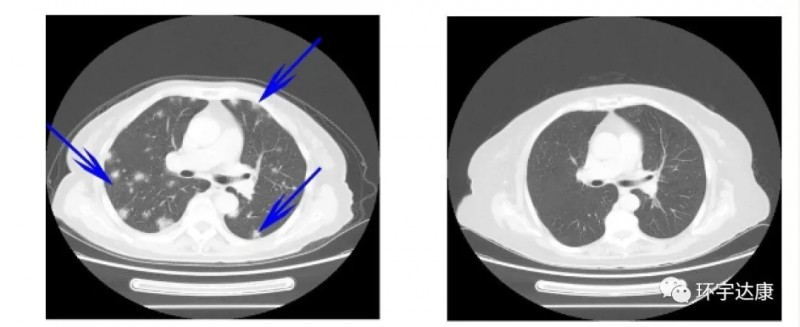

其中一位晚期骨肉瘤患者已经出现了双肺转移,TIL加抗PD1治疗后12周后双肺多个转移(蓝色箭头)完全缓解。

这些结果表明,TILs疗法联合PD-1显着提高了转移性骨肉瘤患者的治疗效果。